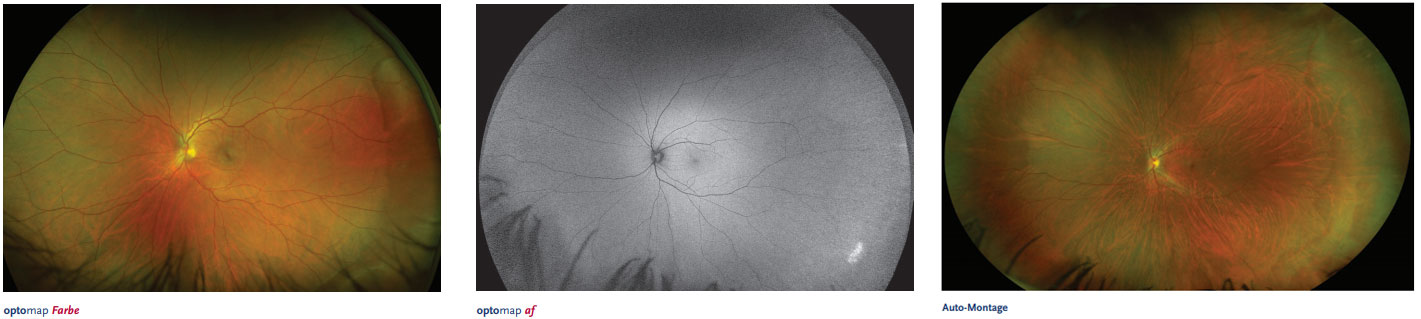

2. OPTOMAP (200Grad-Netzhautdokumentation):

Die Ultra-Weitwinkel Netzhautaufnahme mit dem OPTOMAP ermöglicht eine digitale Panoramaaufnahme der Netzhaut, die über 80% der Netzhaut in einer einzigen Aufnahme darstellen kann. Durch zusätzliche Blickrichtungsänderungen ist im Idealfall nahezu die gesamte Netzhaut im Bild darstellbar, d.h. es kann unter optimalen Bedingungen ein perfektes Screening auf Netzhautveränderungen durchgeführt werden. Die Vorteile dieser Untersuchungsmethode liegen in der Schnelligkeit und im Komfort der Untersuchung, da keine weitstellenden Augentropfen verwendet werden, die die Sehfähigkeit für mehrere Stunden beeinflussen. Weitere Vorteile sind der sehr gute Überblick über die nahezu gesamte Netzhaut, so dass keine Einzelheiten verloren gehen und die Möglichkeit der Dokumentation, so dass alle Befunde im Verlauf vergleichbar sind. Weiterhin gibt es die Möglichkeit der Darstellung der Autofluoreszenz, welche von besonderer Bedeutung bei der Makuladegeneration ist. Zusätzlich kann das OPTOMAP sehr gut bei Kindern durchgeführt werden. Wichtig ist, dass es in einigen Fällen sinnvoll ist, für die Diagnose von wichtigen Einzelheiten die konventionelle Methode mit dem Kontaktglas zusätzlich durchzuführen.